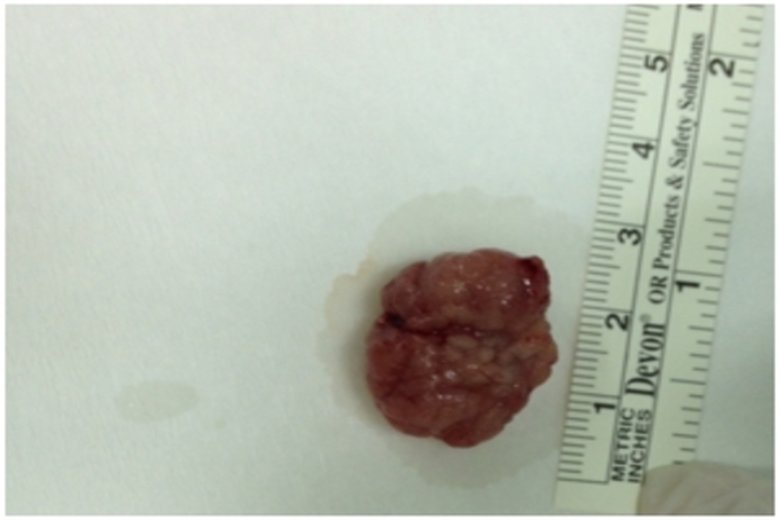

醫生操作時將一根導管與攝像儀探入大腸內,以查看大腸內部的狀況。圖為內視鏡光源照射瘜肉組織外觀(衛福部朴子醫院提供)

【新唐人亞太台 2015 年 12 月 11 日訊】家族有患大腸瘜肉,或家族史患有大腸癌或線性瘜肉,是罹患大腸癌的高危險群。大腸瘜肉演變為大腸癌之前症狀不明顯,除非瘜肉已經大於1公分或已到晚期才會出現不適的症狀。大腸內視鏡做檢查,可早期發現大腸性瘜肉並切除,有效降低大腸癌的發生率。